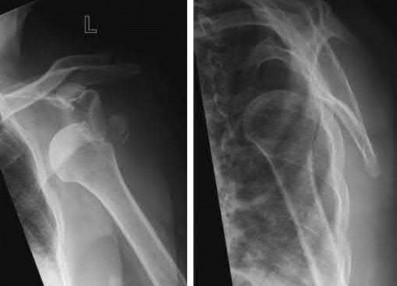

Question 12:

A 55-year-old patient presents with a slowly enlarging, painful mass in the proximal humerus. Biopsy reveals a hyaline cartilage matrix with cellular atypia, confirming a diagnosis of central conventional chondrosarcoma. Which of the following genetic mutations is most frequently identified in this specific tumor?

Correct Answer: IDH1 / IDH2

Explanation:

Mutations in the isocitrate dehydrogenase genes, IDH1 and IDH2, are found in up to 50-60% of central conventional chondrosarcomas and enchondromas. EXT1 and EXT2 mutations are characteristic of multiple hereditary exostoses (osteochondromas). GNAS mutations are seen in fibrous dysplasia. TP53 and RB1 mutations are hallmark aberrations in osteosarcoma.